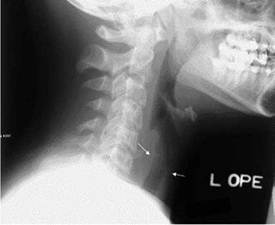

Como es de vuestro conocimiento la traqueítis bacteriana se presenta en niños de un mes a 6 años. Se inicia con síntomas prodrómicos de una infección respiratoria superior de pocos días de duración (temperatura leve y tos), seguidos de dificultad respiratoria progresiva, tos perruna con esputo purulento abundante, estridor y fiebre elevada. Los agentes causales más usuales son: S aureus, Moraxella catarrhalis, S pneumoniae y H influenzae tipo b.28 La radiografía lateral de cuello, muestra la presencia de membranas intraluminales e irregularidades en la mucosa traqueal (figura 5). Se diferencia de la LT viral porque cursa con fiebre elevada y un estado toxico-infeccioso severo y no responde al tratamiento con epinefrina nebulizada.28 La enfermedad puede progresar rápidamente hasta la obstrucción completa de las vías respiratorias.11

Figura N°5. Radiografía lateral de cuello que muestra La presencia de membranas intraluminales e Irregularidades en la pared traqueal